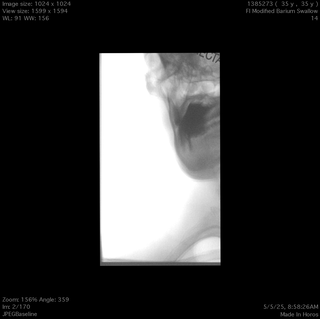

Tonsil surgery did solve the problem of my tonsils hurting, because they were gone, but no resolution of other symptoms. This was a year ago. I’ve been to PT, SLP, and now back to PT while I trial gabapentin for the neurologist. PT#2 discovered a bunch of significant atrophy in my upper right shoulder/back, and, you guessed it it’s all right sided. I’ve since then, thanks to radiopedia and Netter’s, also explored my images and noticed a few other anomalies in my scans, including an extended right thyroid superior cornu which appears to be pressing strongly into my neck also in the general area of pain, and an occipital artery branching off and wrapping around the internal carotid. Frustratingly these also weren’t mentioned on rads reports. My swallow study by the SLP showed obvious asymmetry with my swallow, but the SLP reported it symmetric and radiology apparently doesnt read the A/P view in their modified barium swallow studies? This is not inspiring faith in the academic institution I attended, but what can I possibly know they dont?